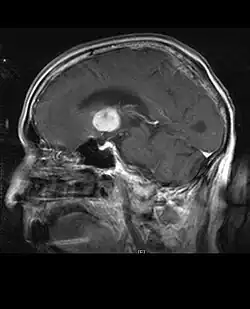

Computertomografie (CT) en magnetische resonantiebeeldvorming (MRI) kunnen neoplasie in de hersenen effectief detecteren. MRI is gevoeliger dan CT voor het identificeren van laesies, maar heeft contra-indicaties voor patiënten met pacemakers, incompatibele prothesen, metalen clips en andere. CT blijft de voorkeursmethode om calcificaties in laesies of boterosie van het kalotje of de basis te detecteren. Het gebruik van contrastmiddelen, die gejodeerd zijn in het geval van CT en paramagnetisch (gadolinium) in het geval van MRI, maakt het verkrijgen van informatie over de vascularisatie en integriteit van de bloed-hersenbarrière mogelijk, een betere definitie van de tumorachtige tumor vergeleken tot het omringende oedeem en het genereren van hypothesen over de mate van maligniteit. Het radiologisch onderzoek maakt ook een beoordeling mogelijk van de mechanische effecten en de daaruit voortvloeiende veranderingen in hersenstructuren als gevolg van de tumor, zoals hydrocefalus en hernia's, waarvan de effecten fataal kunnen zijn. Ten slotte kan deze diagnostiek, ter voorbereiding op een operatie, worden gebruikt om de locatie van de laesie of de infiltratie van de tumor in vitale delen van de hersenen te bepalen. Voor dit doel is MRI efficiënter dan CT omdat het driedimensionale beelden kan opleveren. Diagnostische radiologische beeldvormingshulpmiddelen benadrukken de verandering in neoplastisch weefsel in vergelijking met normaal hersenparenchym (door veranderingen in elektronisch afgebeelde weefseldichtheid op CT en signaalintensiteit op MRI). Zoals de meeste pathologische weefsels zijn tumoren ook herkenbaar aan een verhoogde ophoping van intracellulair water. In het computertomogram lijken ze hypodens, dwz met een lagere dichtheid dan het hersenparenchym, in het kernmagnetische resonantietomogram met spin-roosterrelaxatie hypointenseen in spin-spin ontspanning evenals proton weging (PD) hyperintens.

Aan -MRI toont een intracraniële tumor als een massieve laesie die na gebruik van het contrastmiddel meer luminescent kan worden. Er is echter altijd een signaalafwijking in -Magnetic resonance imaging, die de aanwezigheid van neoplasie of vasogeen oedeem aangeeft. Gewoonlijk is verhoogde luminescentie (contrastversterking) indicatief voor een tumor met een hogere graad van maligniteit. Kenmerkend voor glioblastoom is een contrastring, waarbij het lichtgevende deel overeenkomt met het vitale deel van de kwaadaardige tumor en het donkerdere -hypointens gebied dat overeenkomt met weefselnecrose.